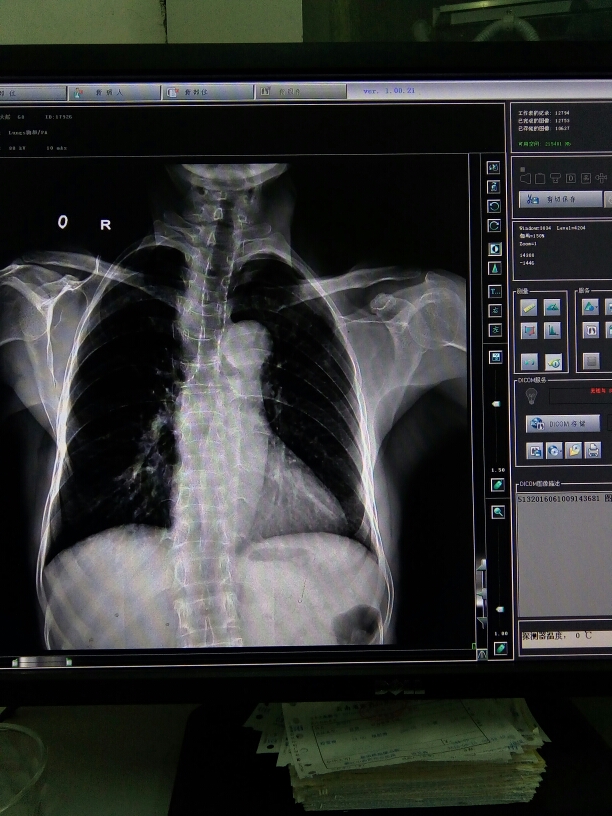

X13985:主气管

体检 。

气管、双侧主支气管软骨钙化。

气管及左右主支气管见高密度影,考虑:气管及左右主支气管软骨钙化。